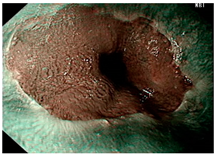

| Image | GERD Endoscopy Grading | Gerd-VGGNet | GerdNet-RF |

|---|---|---|---|

![]() | LA grade A–B | LA grade A–B | LA grade A–B |